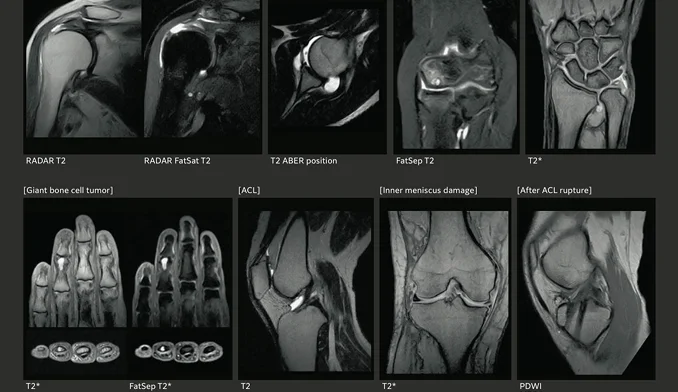

Explore images and visuals of our state-of-the-art Open MRI technology in action. From the open, patient-friendly design to advanced AI imaging, see how we combine innovation, comfort, and precision to transform the MRI experience.